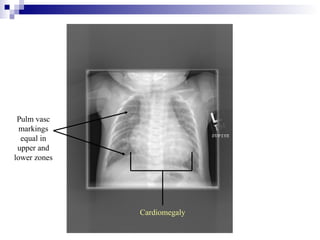

Pulm vasc

markings

equal in

upper and

lower zones

Cardiomegaly

Pulm vasc markings equal in upper and lower zones Cardiomegaly